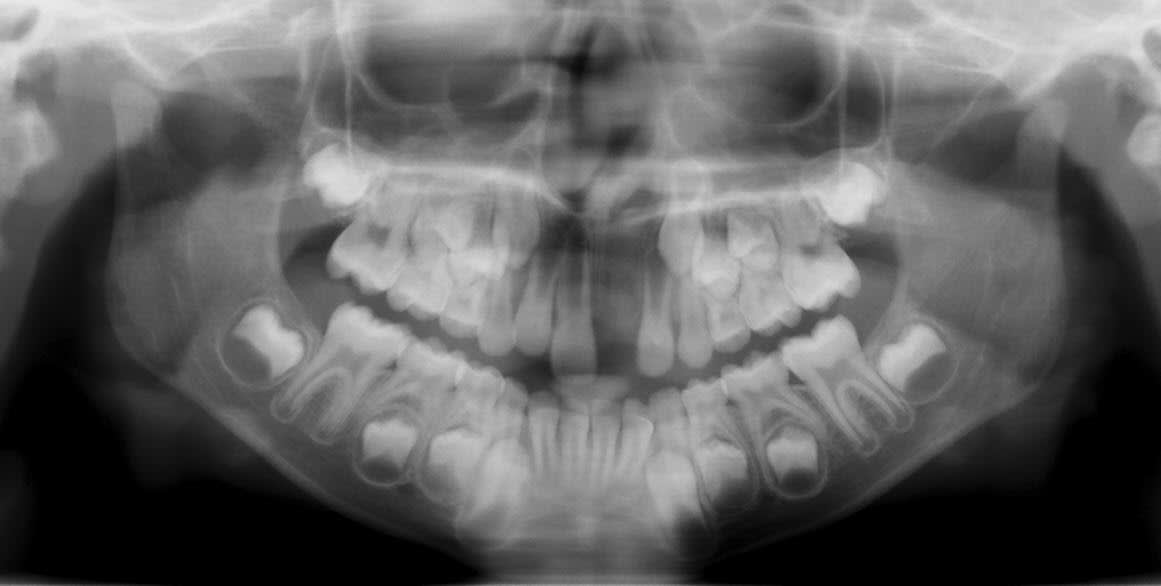

Voici les clichés radios demandés. Cette jeune fille a 7 ans.

Qu'est-ce que tu proposes ?

Je crois que la décision orthodontique peut attendre car les racines des incisives n'ont pas fini leur formation. Il reste deux problèmes: le cote esthétique et la classe II!

Un EF classe II pourrait être utile dans un premier temps. Reste le problème esthétique? il faut improviser!